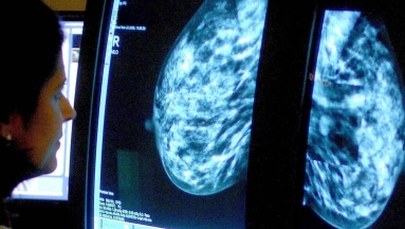

Jak "wyłapać" raka w akcji - jak to określacie - "Zdążyć przed rakiem"? Mamy badania USG, wiemy o mammografii, szeregu innych badań - co, kiedy, w jakim wieku?

Następnym elementem jest skierowanie się do lekarza, który wykona badanie sonograficzne - są to badania podstawowe u kobiet do 40. roku życia. Natomiast po 40. roku życia, a już na pewno po 50., badaniem podstawowym będzie badanie mammograficzne. Między 40. a 50. rokiem życia lekarz badający pacjentkę będzie kierował - czy mammografia czy USG, czy oba.